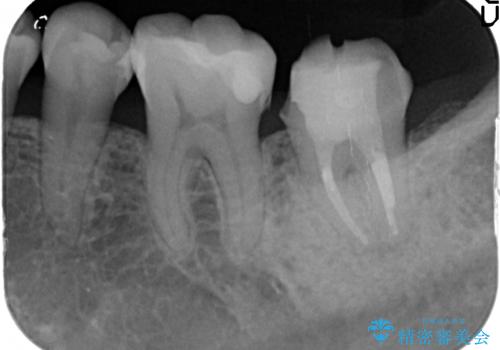

- 他院にて根管治療を行っていたが、痛みが引かないため当院での診療を希望された方の症例です。

改めて再根管治療を行い、症状の緩解を確認後、オールセラミッククラウンによる補綴を行いました。